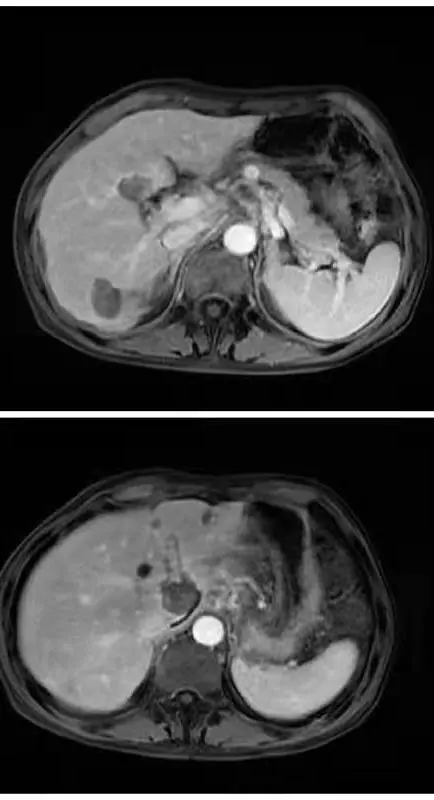

經術前充分評估和準備後,黃斌往患者腹腔內注入約1000ml的溫生理鹽水,人為造成腹腔積液,分離周圍胃腸道和膽囊,保護其不受熱損傷的同時,將肝門部的腫瘤完全消融乾淨。而尾狀葉的腫瘤透過超聲造影的引導,消融針在僅有5mm空間的進針路徑穿行,避開動脈血管和膽管,將消融針精準地插入瘤體內使之滅活。整個手術過程猶如行走在懸崖峭壁的鋼絲,需要十足的耐心和精準的操作,患者術後當天下午就下床活動,術後1周增強磁共振和超聲造影均提示腫瘤完全滅活。

∆ 術後一週增強磁共振顯示病灶完全消融